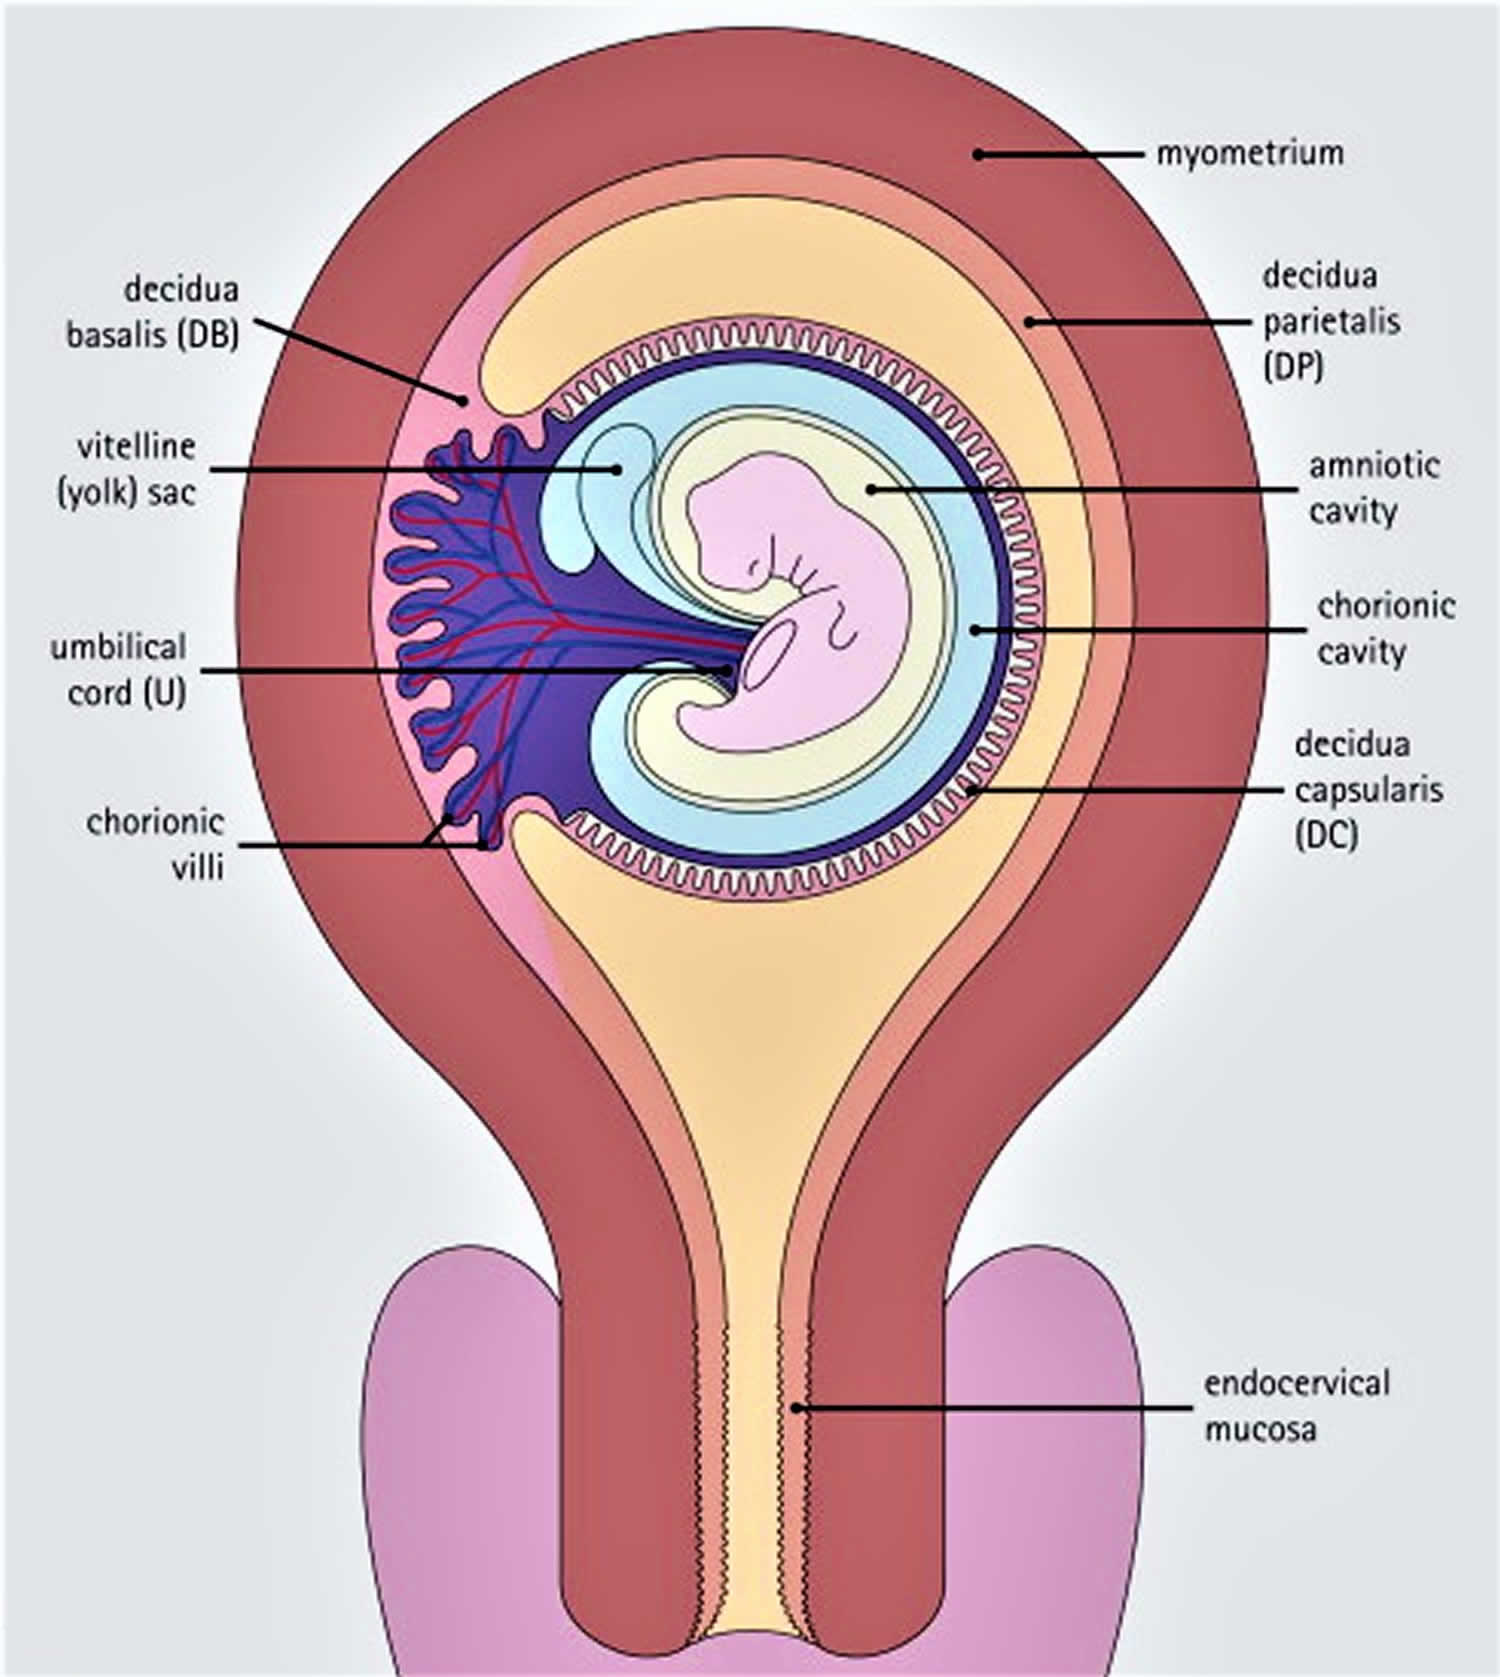

Decidua Definition Layers Of Decidua Formation Function